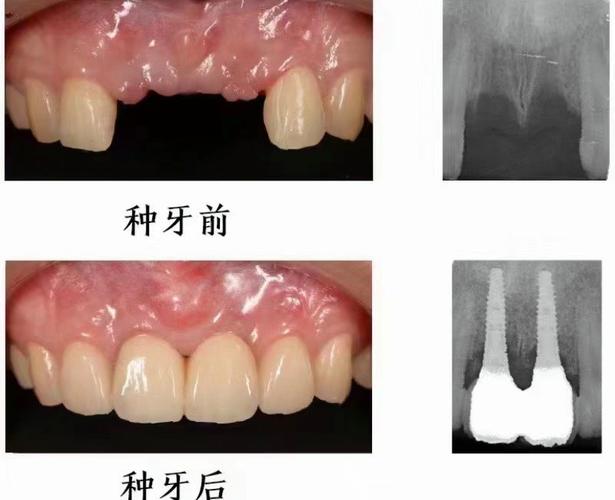

种植牙的原理是通过外科手术将纯钛种植体植入牙槽骨内,作为人工牙根,待其与骨组织结合(骨结合)后,再安装基台和牙冠,实现功能与美观的恢复,全口无牙患者能否种牙,核心取决于牙槽骨的条件——包括骨量(高度、宽度、密度)、骨质量以及是否有影响愈合的全身因素。